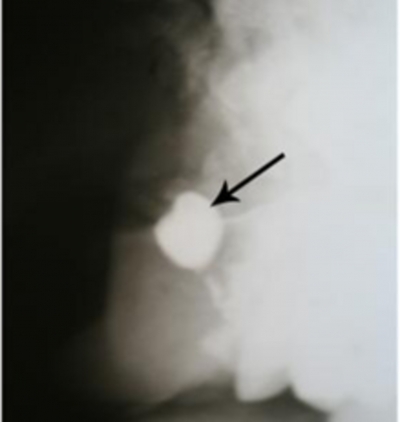

Medicul care l-a consultat a ramas masca in momentul in care a descoperit in nasul pacientului o masea lunga de 1 centimetru. Dupa ce i-a fost extras obiectul, un medic stomatolog a confirmat ca este vorba de un dinte, insa nu a putut explica motivul pentru care s-a dezvoltat tocmai in nas.

Pacientul, un tanar din varsta de 22 de ani, avea dantura completa, iar dintele care i-a cauzat atata suferinta era practic in plus.

De cand a scapat de acest dintele, pacientul nu a avut sangerari nazale. Cazul sau a fost prezentat in American Journal of Case Reports. John Hellestein, dentist si medic legist la Universitatea din Iowa, spune ca dintii in plus nu sunt un efnomen rar, dar de obicei acestia nu cresc in nas.